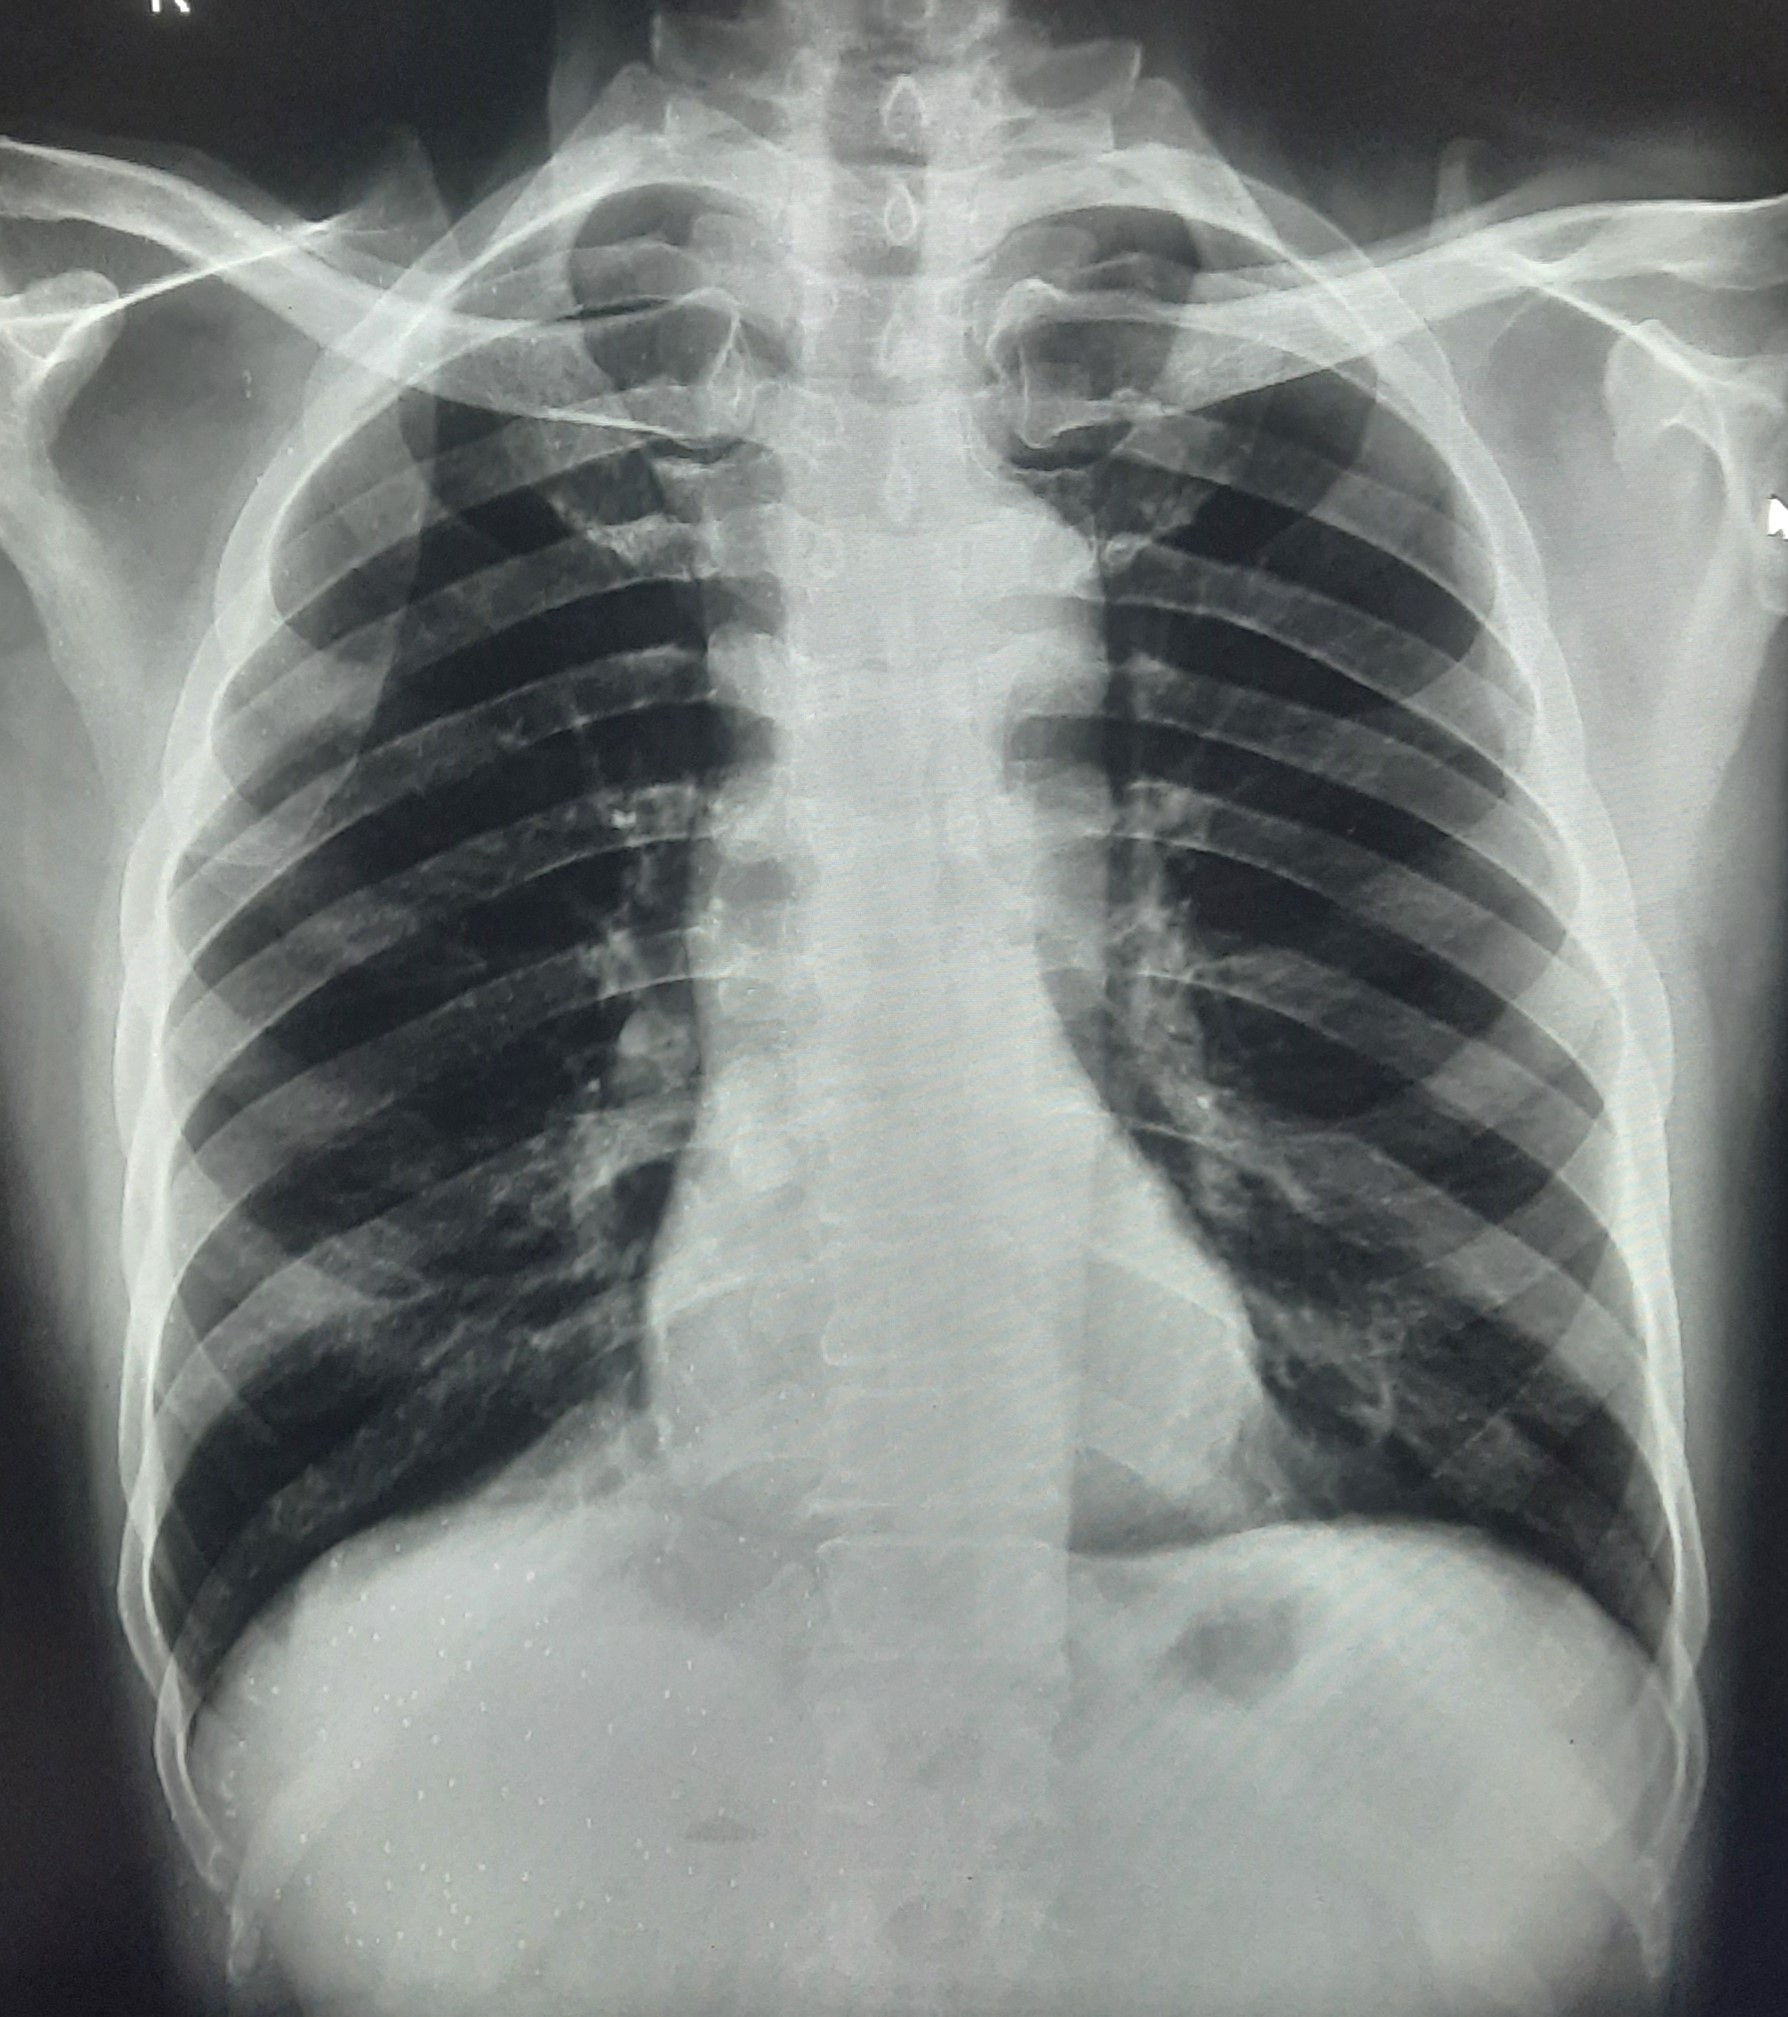

| 251 | IGGMC, Nagpur, Nagpur | P2 | 29-4221 | Ganpat Gaikawad | Consent taken on Paper | 70 Yrs. |

Provisional Diag : post TB sequele?

Final Diag : Fibrosis |

Non-TB Case (Confirmed) | Fibrosis | Abnormality visible on x-ray |